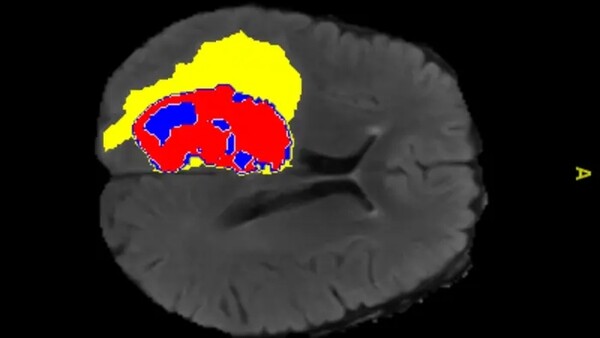

В университете им. Монаша (Австралия) испытали новый алгоритм обучения искусственного интеллекта, похожий на известную в медицине процедуру запроса «второго мнения», которой пользуются при решении сложных медицинских вопросов. Система с искусственным интеллектом, анализирующая рентгеновские снимки, состоит их двух частей: одна часть анализирует снимки, выделяя на них зоны с подозрением на патологические изменения, а другая часть оценивает результаты работы первой, сравнивая их с базой снимков, проанализированных специалистами. Новый алгоритм в испытаниях на общедоступных базах медицинских данных показал в среднем результаты лучше, чем самые лучшие из известных алгоритмов, утверждают исследователи. Статья с описанием алгоритма опубликована в журнале Nature Machine Intelligence.